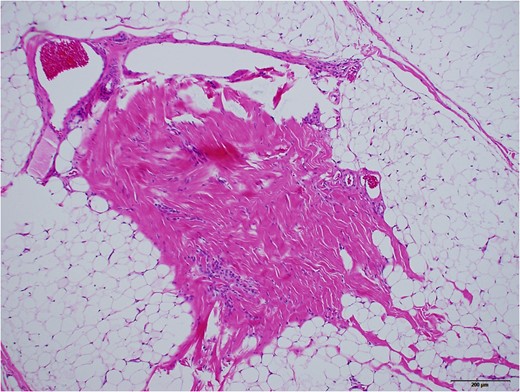

Grossly, protruded part of the mass was covered with sparsely haired skin. Sub-conjunctival part was covered with thin capsule with vasculatures (Fig. 5). Histopathologically, most part of the mass was composed of mature adipose tissue, lobuled by fibrous septum with vasculatures (Fig. 6). Outer surface was covered with squamous epidermis with normal rete ridge. In dermal layer, appendages, including hair follicles, sebaceous glands and sweat glands were seen (Fig. 7). Dense fibrous tissue was seen surrounded by the adipose tissue. This was assumed to be the link of palpebral tarsal plate (Fig. 8). No lacrimal grand tissue was identified.

Higher magnified surface area, taken with ×10 objective lens. Black bar represents 200 μm. Mature hair follicles, sebaceous glands, and sweat glands were observed.